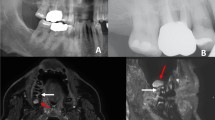

64-year-old patient with known periodontitis. a OPT and b dental radiograph of the tooth 46 after root canal treatment showing no distinct radiolucency. c Sagittal and d coronal reconstruction of a 3D STIR sequence showing a bright edema periapical around the root of the treated tooth. The alveolar bone edema on MRI (white arrows) indicates an inflammatory process but might be also associated with physiological changes. Therefore, findings have to be evaluated together with the results from patient anamnesis and clinical examination

53-year-old patient with symptomatic periodontitis of the tooth 41. A distinctive periapical radiolucency (white arrows) can be seen on OPT (a) and dental radiograph (b). The coronal (c) and axial (d) reconstructions of a 3D STIR sequence show a larger bone marrow edema around the periapical lesion, indicating a larger inflammatory reaction (white arrows)